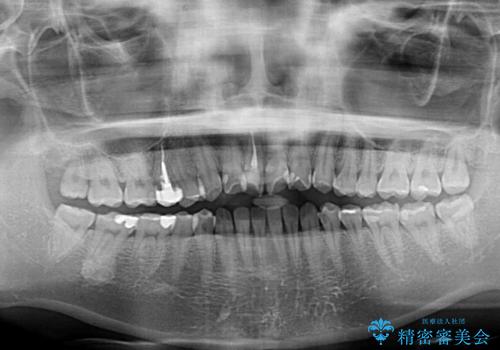

- 上下前歯のデコボコを気にして来院された患者様です。

ワイヤー矯正でもマウスピース矯正でも可能でしたが、短期間で、自身の手を煩わせることなく治療を行いたいとのことで、ワイヤー装置にて矯正治療を行うこととしました。

ご本人の中では2年近くかかるものと思っていたそうですが、1年で治療を終えることができ、大変満足していらっしゃいました。